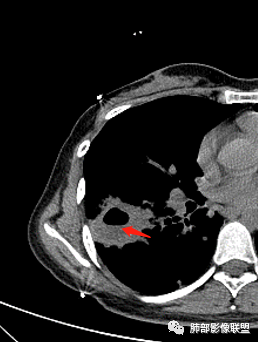

患者青年女性咳嗽、咳痰1月,加重1周,发热3天。患者1月前受凉后出现咳嗽,咳少量白色痰,1周前咳嗽加重,痰量增多,为黄白色黏痰,偶有痰中带血,轻微胸闷,近3天来出现发热,最高体温38.4℃,伴乏力,食欲下降。辅助检查:血常规白细胞及中性分类 血沉 CRP均增高。胸CT:右肺下叶前基底段实变病灶内可见空洞,洞内可见气液平面,病灶周围及右肺下叶背段可见树芽征 、结节。经抗感染治疗,基底段病灶较前缩小,背段病灶 融合 增大。考虑良性病变,空洞性肺结核合并细菌感染。

青年女性,亚急性病程,呼吸道感染症状,影像:右肺下叶厚壁空洞,内壁光滑,似有液平,外缘分叶、收缩+膨隆,支气管树芽,腺泡结节,界限较为清晰,近端支气管增厚,纵隔淋巴结肿大,强化不均匀;抗感染治疗后,团块短期内似有缩小,背段结节略增大,考虑感染,第一个排除肿瘤,影像上更支持结核,临床进程上支持脓肿,不除外二元因素,结核并感染

29岁女性,既往体健。咳嗽咳痰(白黏痰)一月,加重一周(黄白痰),发热3天伴咯血。血常规:中性粒、CRP升高,血沉增高。CT:右肺下叶不规则厚壁空洞伴散在树芽、小叶中心结节。空洞内壁光滑,似见液平。无胸腔积液及明显纵膈肿大淋巴结。予左氧及美洛西林舒巴坦治疗12天,临床症状减轻。复查CT见空洞明显吸收缩小,增强见薄壁空洞,内有液平,引流支气管增厚。考虑感染;是单纯细菌感染还是结核感染?还是细菌合并结核?建议痰找抗酸杆菌,痰培养,并继续复查肺部CT,可完善支气管镜检查。

年轻女性:右肺下叶背段,基底段不规则厚壁空洞,内壁光滑,且内壁上有坏死组织,第一次有液气平面,边缘分叶、膨隆、平直,周围多发腺泡结节,树芽,内侧支气管有狭窄。抗感染治疗后空洞缩小,但腺泡结节变化不大,考虑:肺结核合并伴感染?

2.右肺下叶片状影、结节影、硬树丫。单发空洞伴液平,内壁规则,外壁较清楚。相关支气管壁增厚。

结核空洞相对薄壁且很少液平,如此明显洞内积液也会怀疑合并细菌等感染。